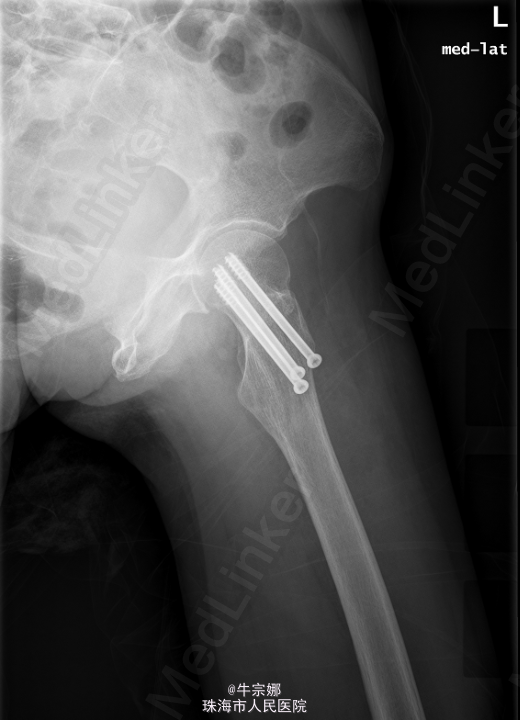

初步诊断:左股骨颈骨折.全麻下行左股骨颈骨折闭合复位内固定术. 取以左股骨粗隆下方约7cm的外侧经皮切口约3cm,C臂机引导下在左股骨粗隆下方约6cm、5cm、4cm处依次钻入3枚导针达股骨头部,见导针位置好,骨折对位对线良好,测深,分别旋入三枚空心拉力螺钉。再次透视位线良好。拔除导针,予以皮肤缝合。